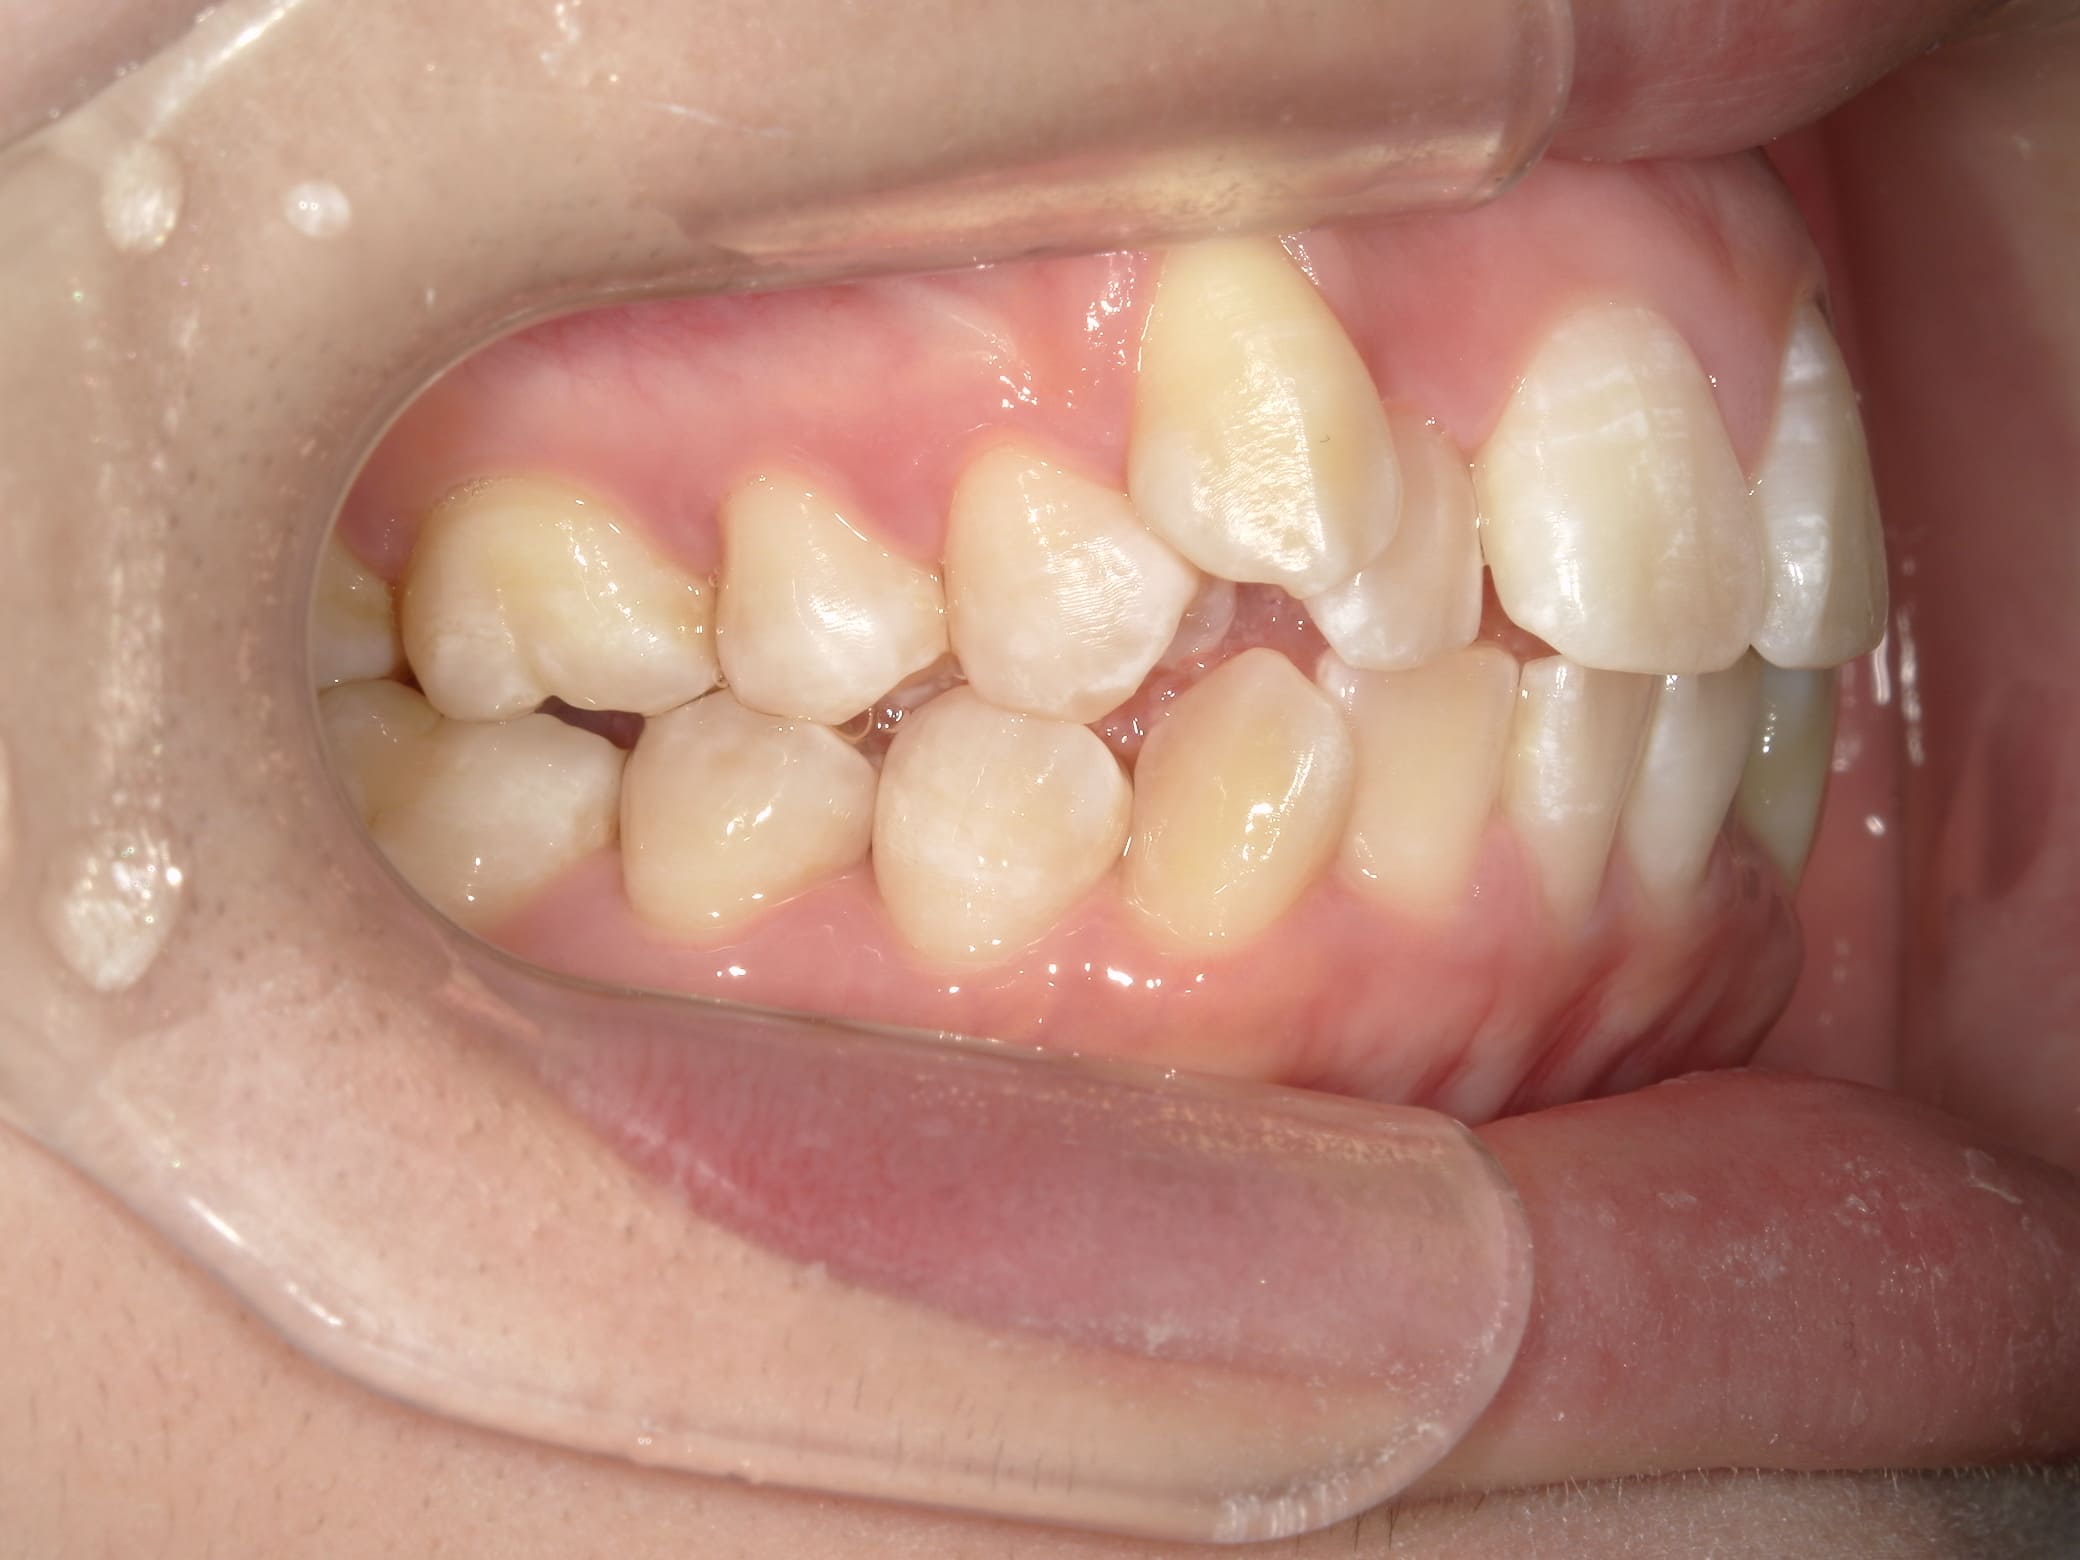

| 年齢・性別 | – |

|---|---|

| 主訴 | 叢生が気になる |

| 治療期間・回数 | 2年 |

| 費用 | 935,000円 |